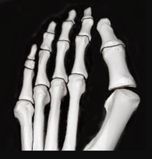

Bunions (Hallux Valgus)Toe Pain/ DeformitiesForefoot Pain & NeuromasFoot ArthritisIngrowing Toenails